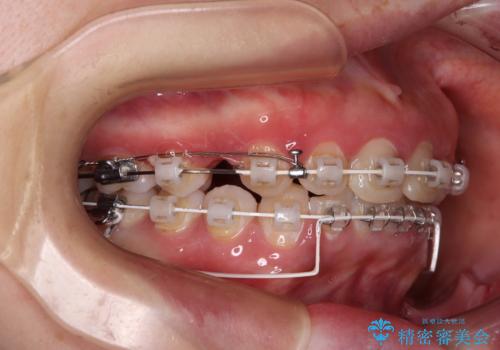

- 矯正装置

- 審美装置

骨格的に上顎が前方にあり、上顎のみの抜歯矯正のため、期間はかかることが予想されましたが、スムーズに移動してくれたおかげで、2年弱の短期間で終えることができました。